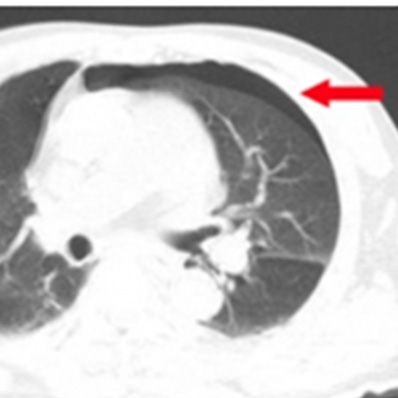

外傷性気胸